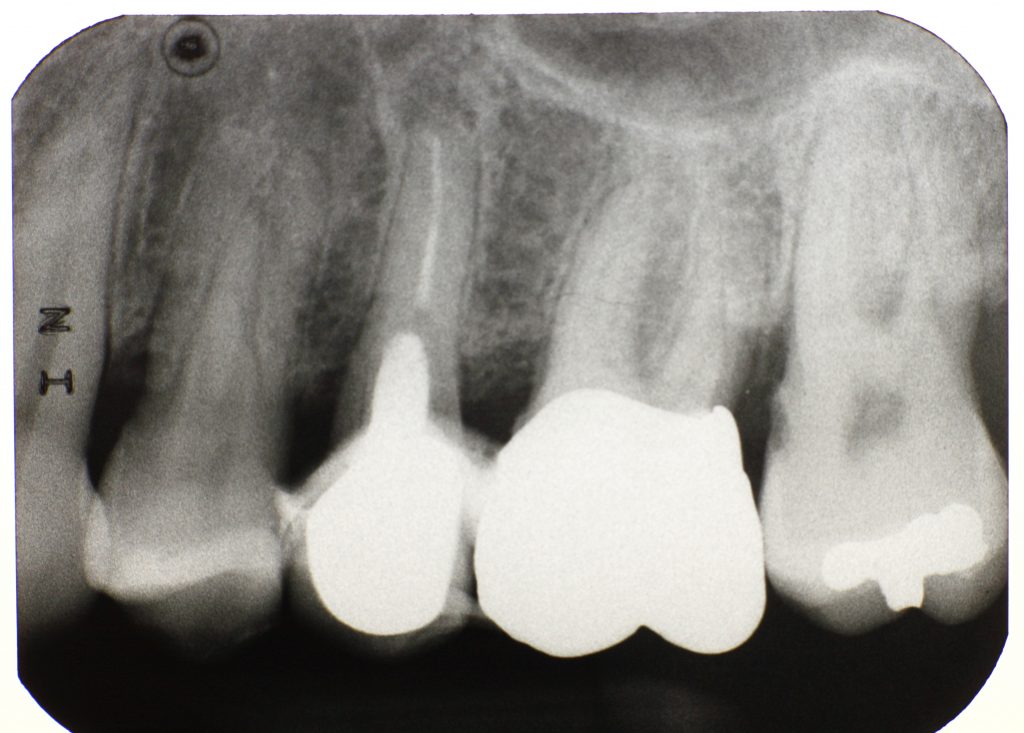

Can A Dentist Remove A Dental Cyst. If it’s small, your dentist might be able to surgically remove it along. Treatment is very effective and often resolves the problem completely. there are many ways to do this, but the best ones are dental cyst surgery and dental cyst treatment (prescribed by a reputable dentist). Another treatment option is marsupialization. Small cysts that are not causing any symptoms. This procedure, performed under local or general anesthesia, aims to completely. however, if the situation is serious, and the cyst (as well as the affected tooth) must be protected from other tissues, you may need to remove the tooth. treating a dentigerous cyst depends on its size. the primary treatment for most dental cysts involves surgical removal. treatment of dental cysts. an oral surgeon can remove a dentigerous cyst, along with the affected tooth. Treatment of dental cysts differs based on their size and location. with large cysts in the jaw bone, ct scans or an mri may be used to plan treatment. If it’s small enough, your dentist might be able to surgically.